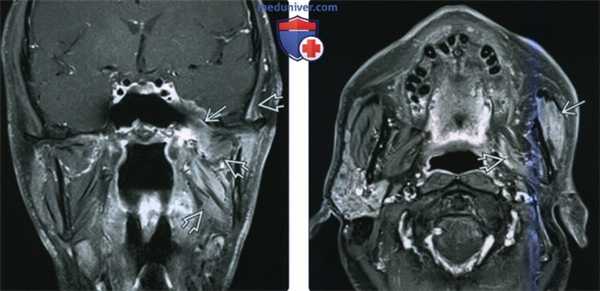

(Слева) КТ без КУ, аксиальная проекция. У пациента с шванномой нижнечелюстного нерва в левом жевательном пространстве обнаружена гетерогенная солидная опухоль с четкими контурами, которая ремоделирует пластинки крыловидного отростка. Такие находки характерны для медленнорастущей опухоли.

(Справа) МРТ Т1ВИ FS c КУ, коронарная проекция, этот же пациент. Шваннома жевательного пространства, которая неравномерно накапливает контрастное вещество. Имеются признаки минимального распространения опухоли в полость черепа через овальное отверстие.

(Слева) КТ в костном окне, аксиальная проекция. У пациента установлен диагноз нейрофиброматоза 2 типа. Правое овальное отверстие расширено, в то время как размеры левого овального отверстия находятся в пределах нормы. Подобное расширение отверстий черепа без разрушения кортикального слоя характерно для доброкачественных опухолей нервной оболочки.

(Справа) МРТ Т1ВИ FS с КУ в коронарной проекции, тот же пациент. Шваннома нижнечелюстного нерва, накапливающая контраст, распространяется от параселлярной области через расширенное овальное отверстие к жевательному пространству носоглотки.